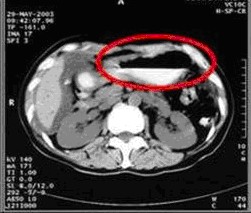

女,49岁。胃体癌晚期,胃窦增厚强化,与周围粘连,腹膜增厚,腹腔广泛转移,伴大量腹水。放/化疗失败,无法手术。治疗方案:腹腔灌注今又生2×1012VP/2次/周,共12周,同时灌注顺铂和5-氟尿嘧啶腹腔,后4周加8次全腹热疗。治疗后:第3周,腹水消失;第8周,胃窦、腹膜和网膜变薄,盆腔结节明显变小。后行手术切除残余胃肿瘤,术中探查全腹和盆腔未扪及肿瘤。术后病检胃肿瘤内未见癌细胞。

治疗前胃窦增厚强化,与周围粘紧,腹膜增厚,大量积水